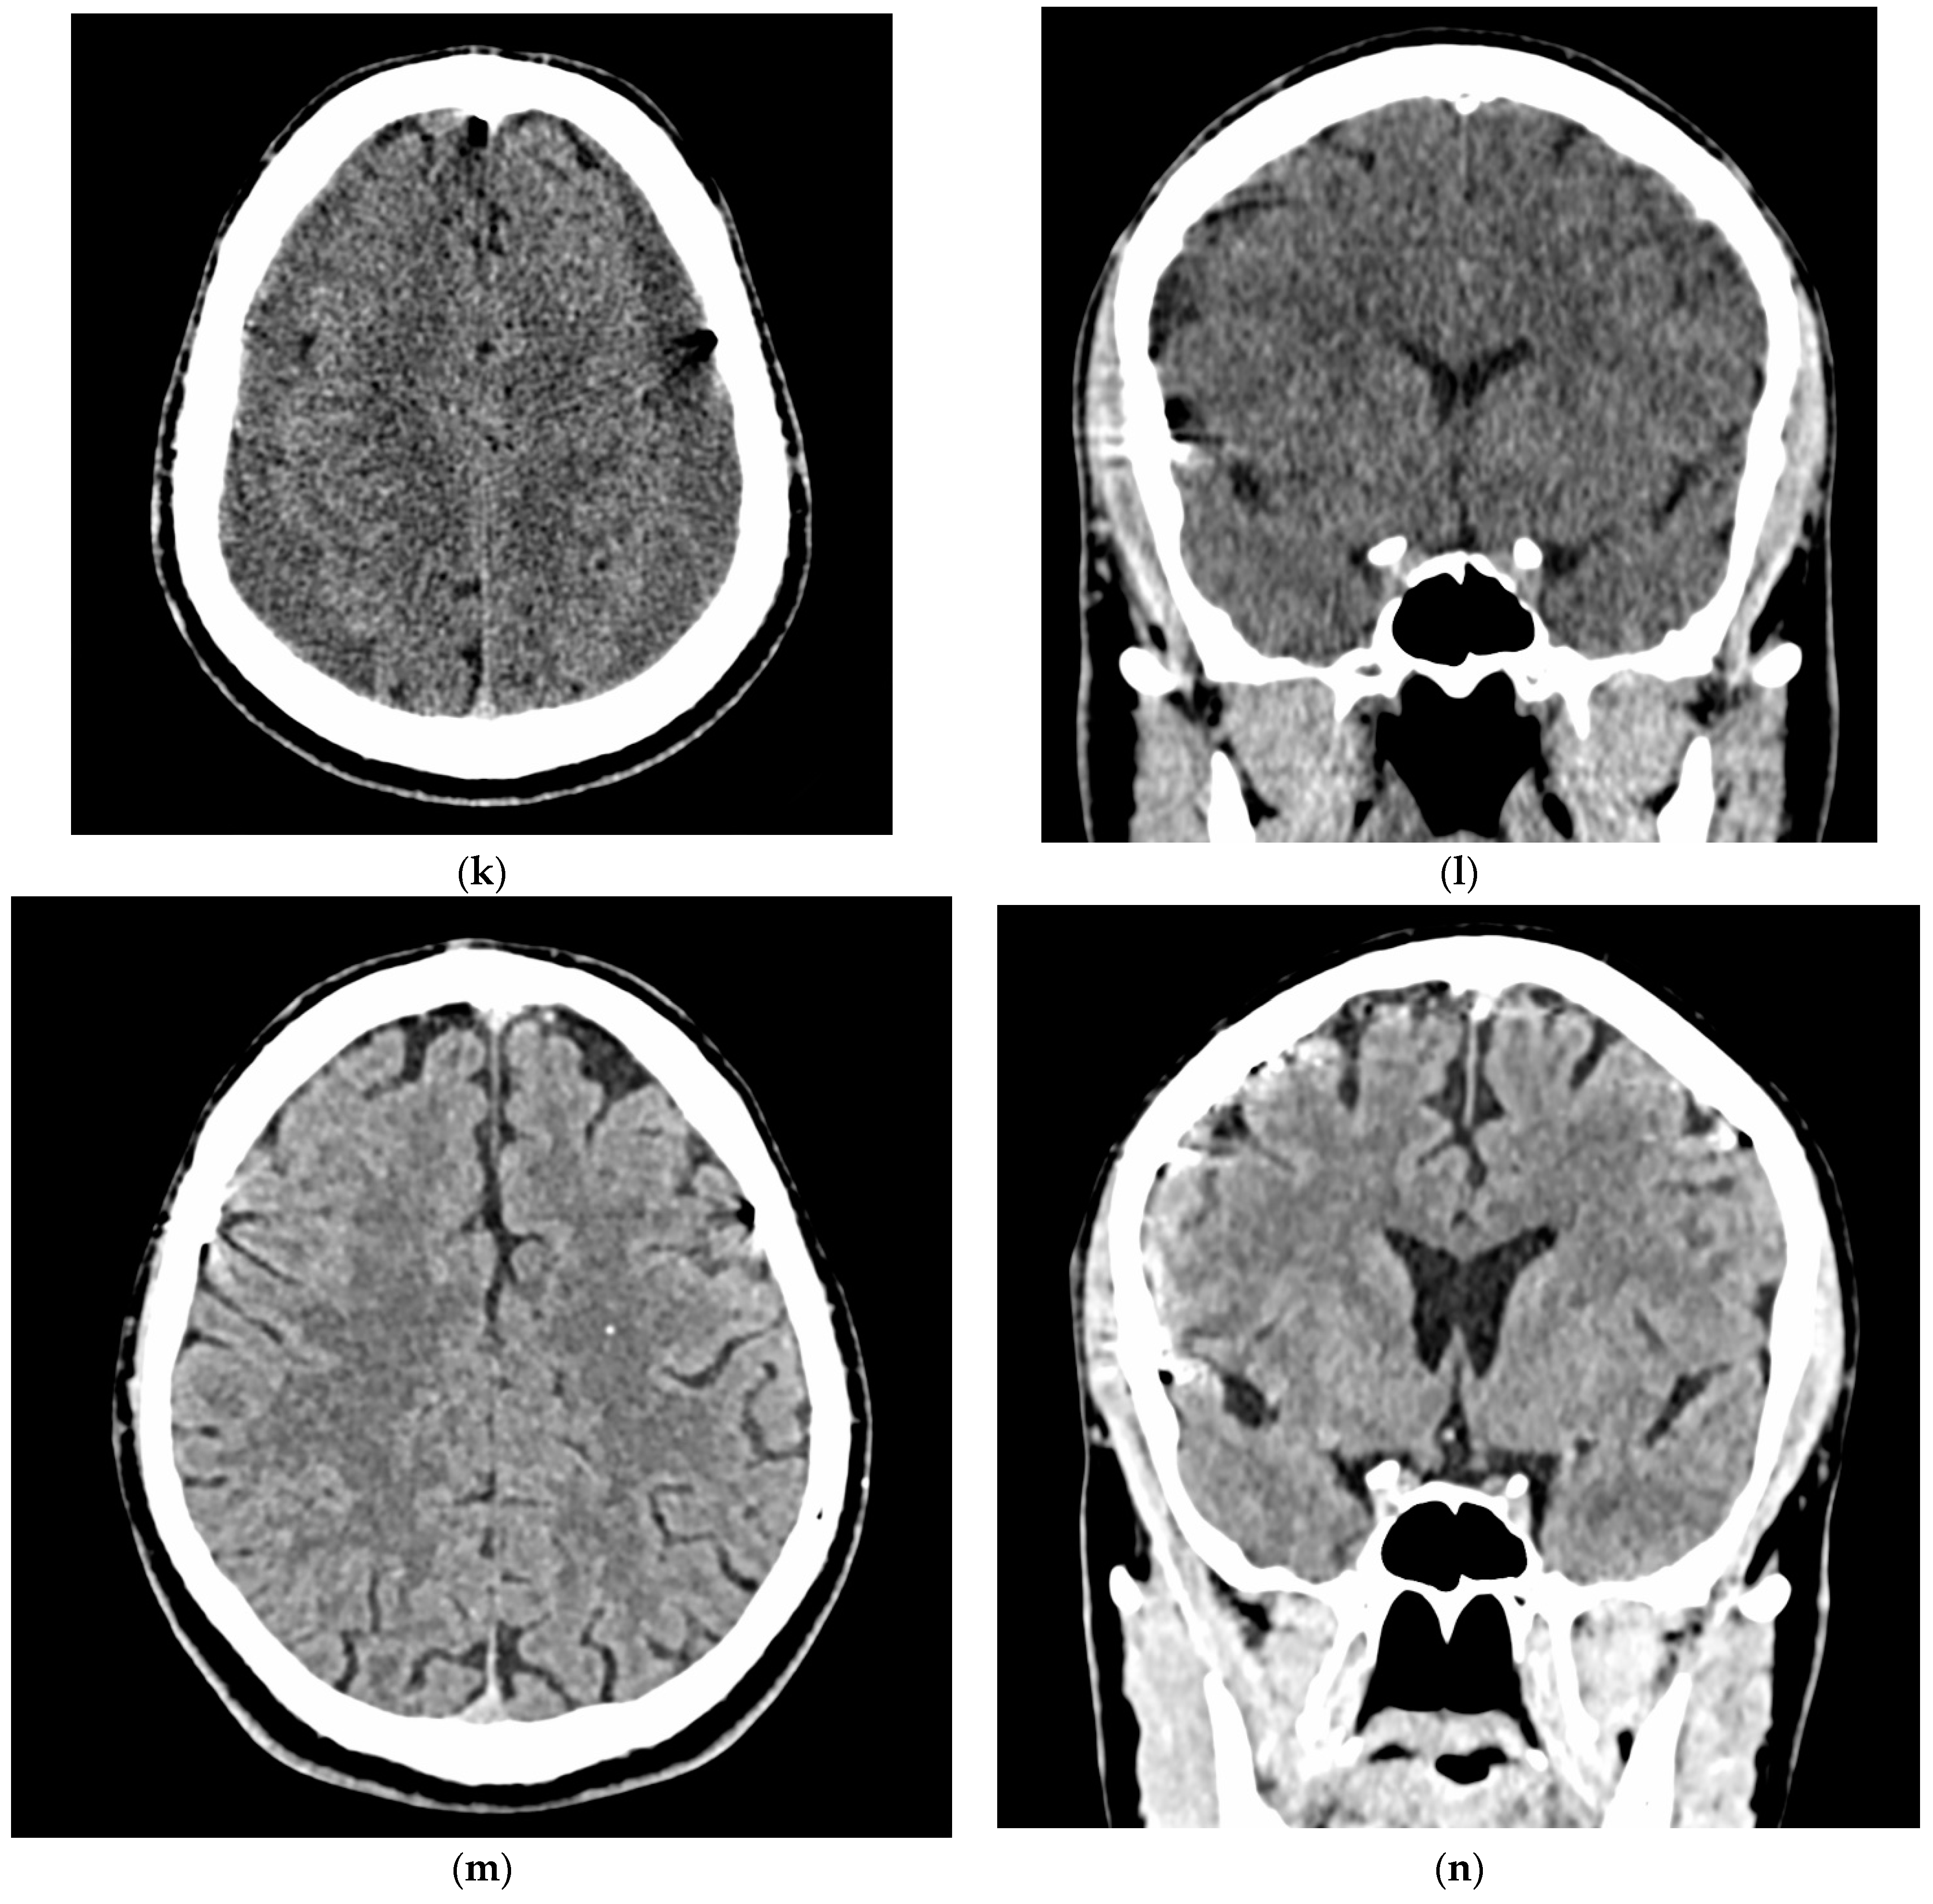

- A 70-year-old patient with left-handed CSDH and a midline shift of 12 mm, motor aphasia, and right-hand hemiparesis.

- A 42-year-old patient with bilateral CSDH that progressively increased during 1.5 months from 54 mL to 69 mL on the right-hand side and from 68 mL to 83 mL on the left-hand side, causing significant compression of both hemispheres and neurological deterioration.

- An 89-year-old patient with bilateral CSDH (no midline shift). There was no apparent connection with an antecedent head injury. However, the patient’s relatives reported that the patient did periodically fall. At the time of admission, the patient presented tetraparesis and a decreased level of consciousness.

3.4. Illustrative Cases